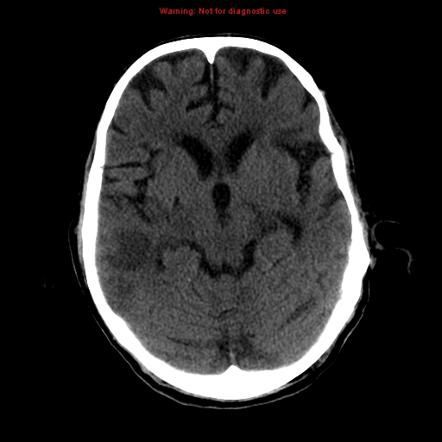

CT scan is the first line investigation of stroke. Ischemic stroke is usually not diagnosed immediately on CT. However, after few hours, following features appear that indicate diagnosis of stroke: - loss of grey and white matter differentiation - parenchymal swelling - lentiform nucleus changes - cortical hypodensity - gyral effacement Reference: https://radiopaedia.org/articles/ischaemic-stroke Image via: https://radiopaedia.org/articles/ischaemic-stroke